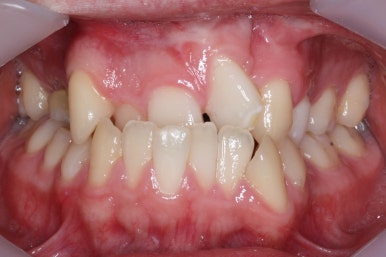

부산구순구개열 키다리아저씨치과에 처음 오셨을 때의 입 안의 모습입니다.

입천장이 갈라져서 어릴 때 봉합 수술을 했기 때문에 그 상처가 굵게 남아있는 것을 볼 수 있습니다. 일반적으로 피부상처도 다른 부위보다 단단하듯이 입천장의 봉합 상처도 매우 단단하게 아물기 때문에 성장에 방해를 주게 됩니다.

가로폭이 매우 좁고 찌그러져 있습니다.

또한 위턱이 앞으로 자라나는 것도 방해해 대부분 앞니가 거꾸로 물리게 됩니다.

또한 가랄져 있던 선에 걸쳐 있는 영구치 일부는 선천결손이 되는 경우가 많습니다.

이번 환자분도 이런 특징을 모두 갖고 계셨습니다.